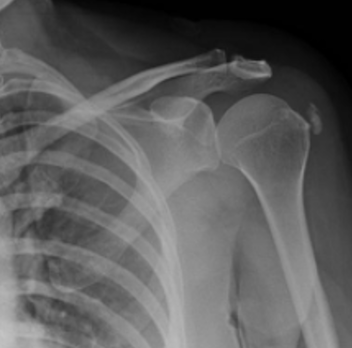

- Plain radiography, MRI, and common imaging findings

- Rotator cuff pathology: tendinosis, partial- and full-thickness tears

- Labral pathology, instability patterns, and biceps tendon disorders